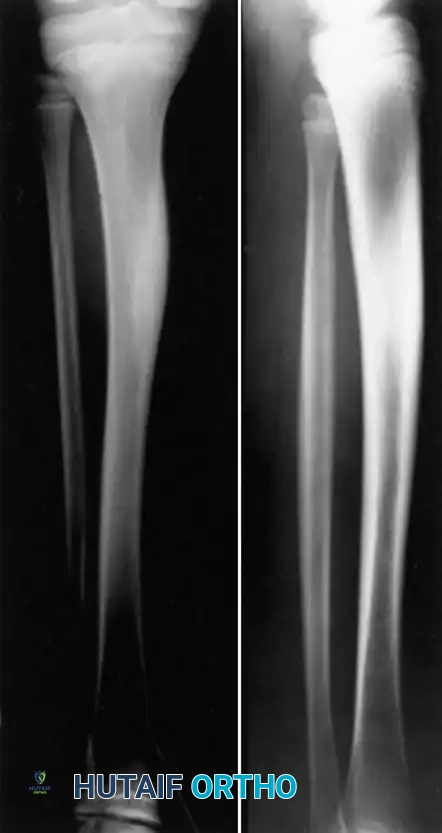

The disease exhibits a strong predilection for the metaphyses of long bones, particularly the tibia, distal femur, and clavicle. Yu et al. also reported the frequent occurrence of vertebra plana (complete vertebral body collapse) associated with this condition.

Radiographically, early lesions are predominantly osteolytic and often bilaterally symmetrical. As the disease progresses into the chronic phase, varying degrees of reactive sclerosis and hyperostosis become prominent.

Image

Clinical Pearl: While whole-body technetium-99m (Tc-99m) bone scanning historically demonstrated bilaterally symmetrical areas of increased radiotracer uptake, Whole-Body MRI (WB-MRI) has now superseded scintigraphy as the gold standard. MRI is highly sensitive for detecting asymptomatic multifocal marrow edema and is critical for excluding pyogenic involvement or malignant processes (e.g., Ewing sarcoma, leukemia).